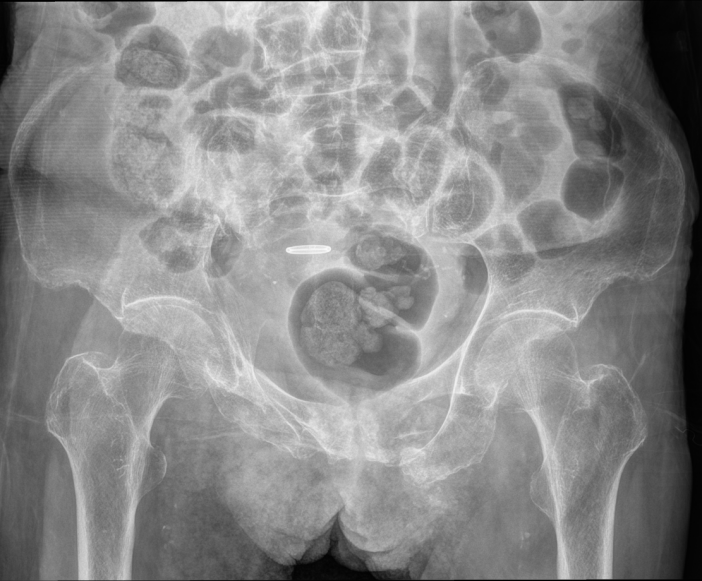

88岁老人骨盆多处骨折。泰康同济多学科协作助其重获活动能力。武汉大学泰康临床学院、泰康同济(武汉)医院(简称泰康同济)骨科副主任医师吴大清团队成功为一名高龄复杂骨盆骨折患者实施了微创手术治疗。术后患者疼痛显著缓解。88岁...